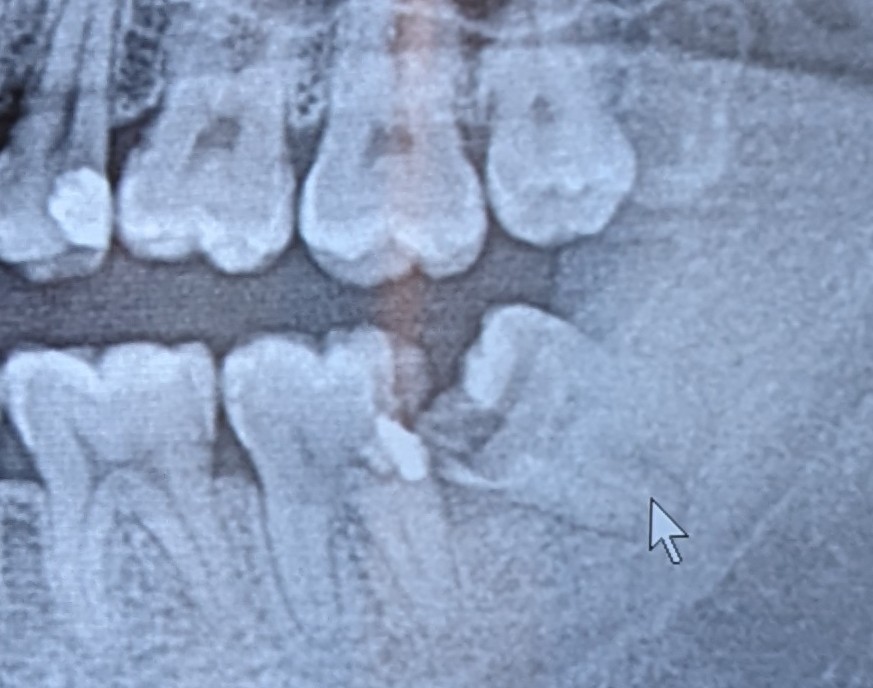

横向きに生えている親知らずの治療はできますか?